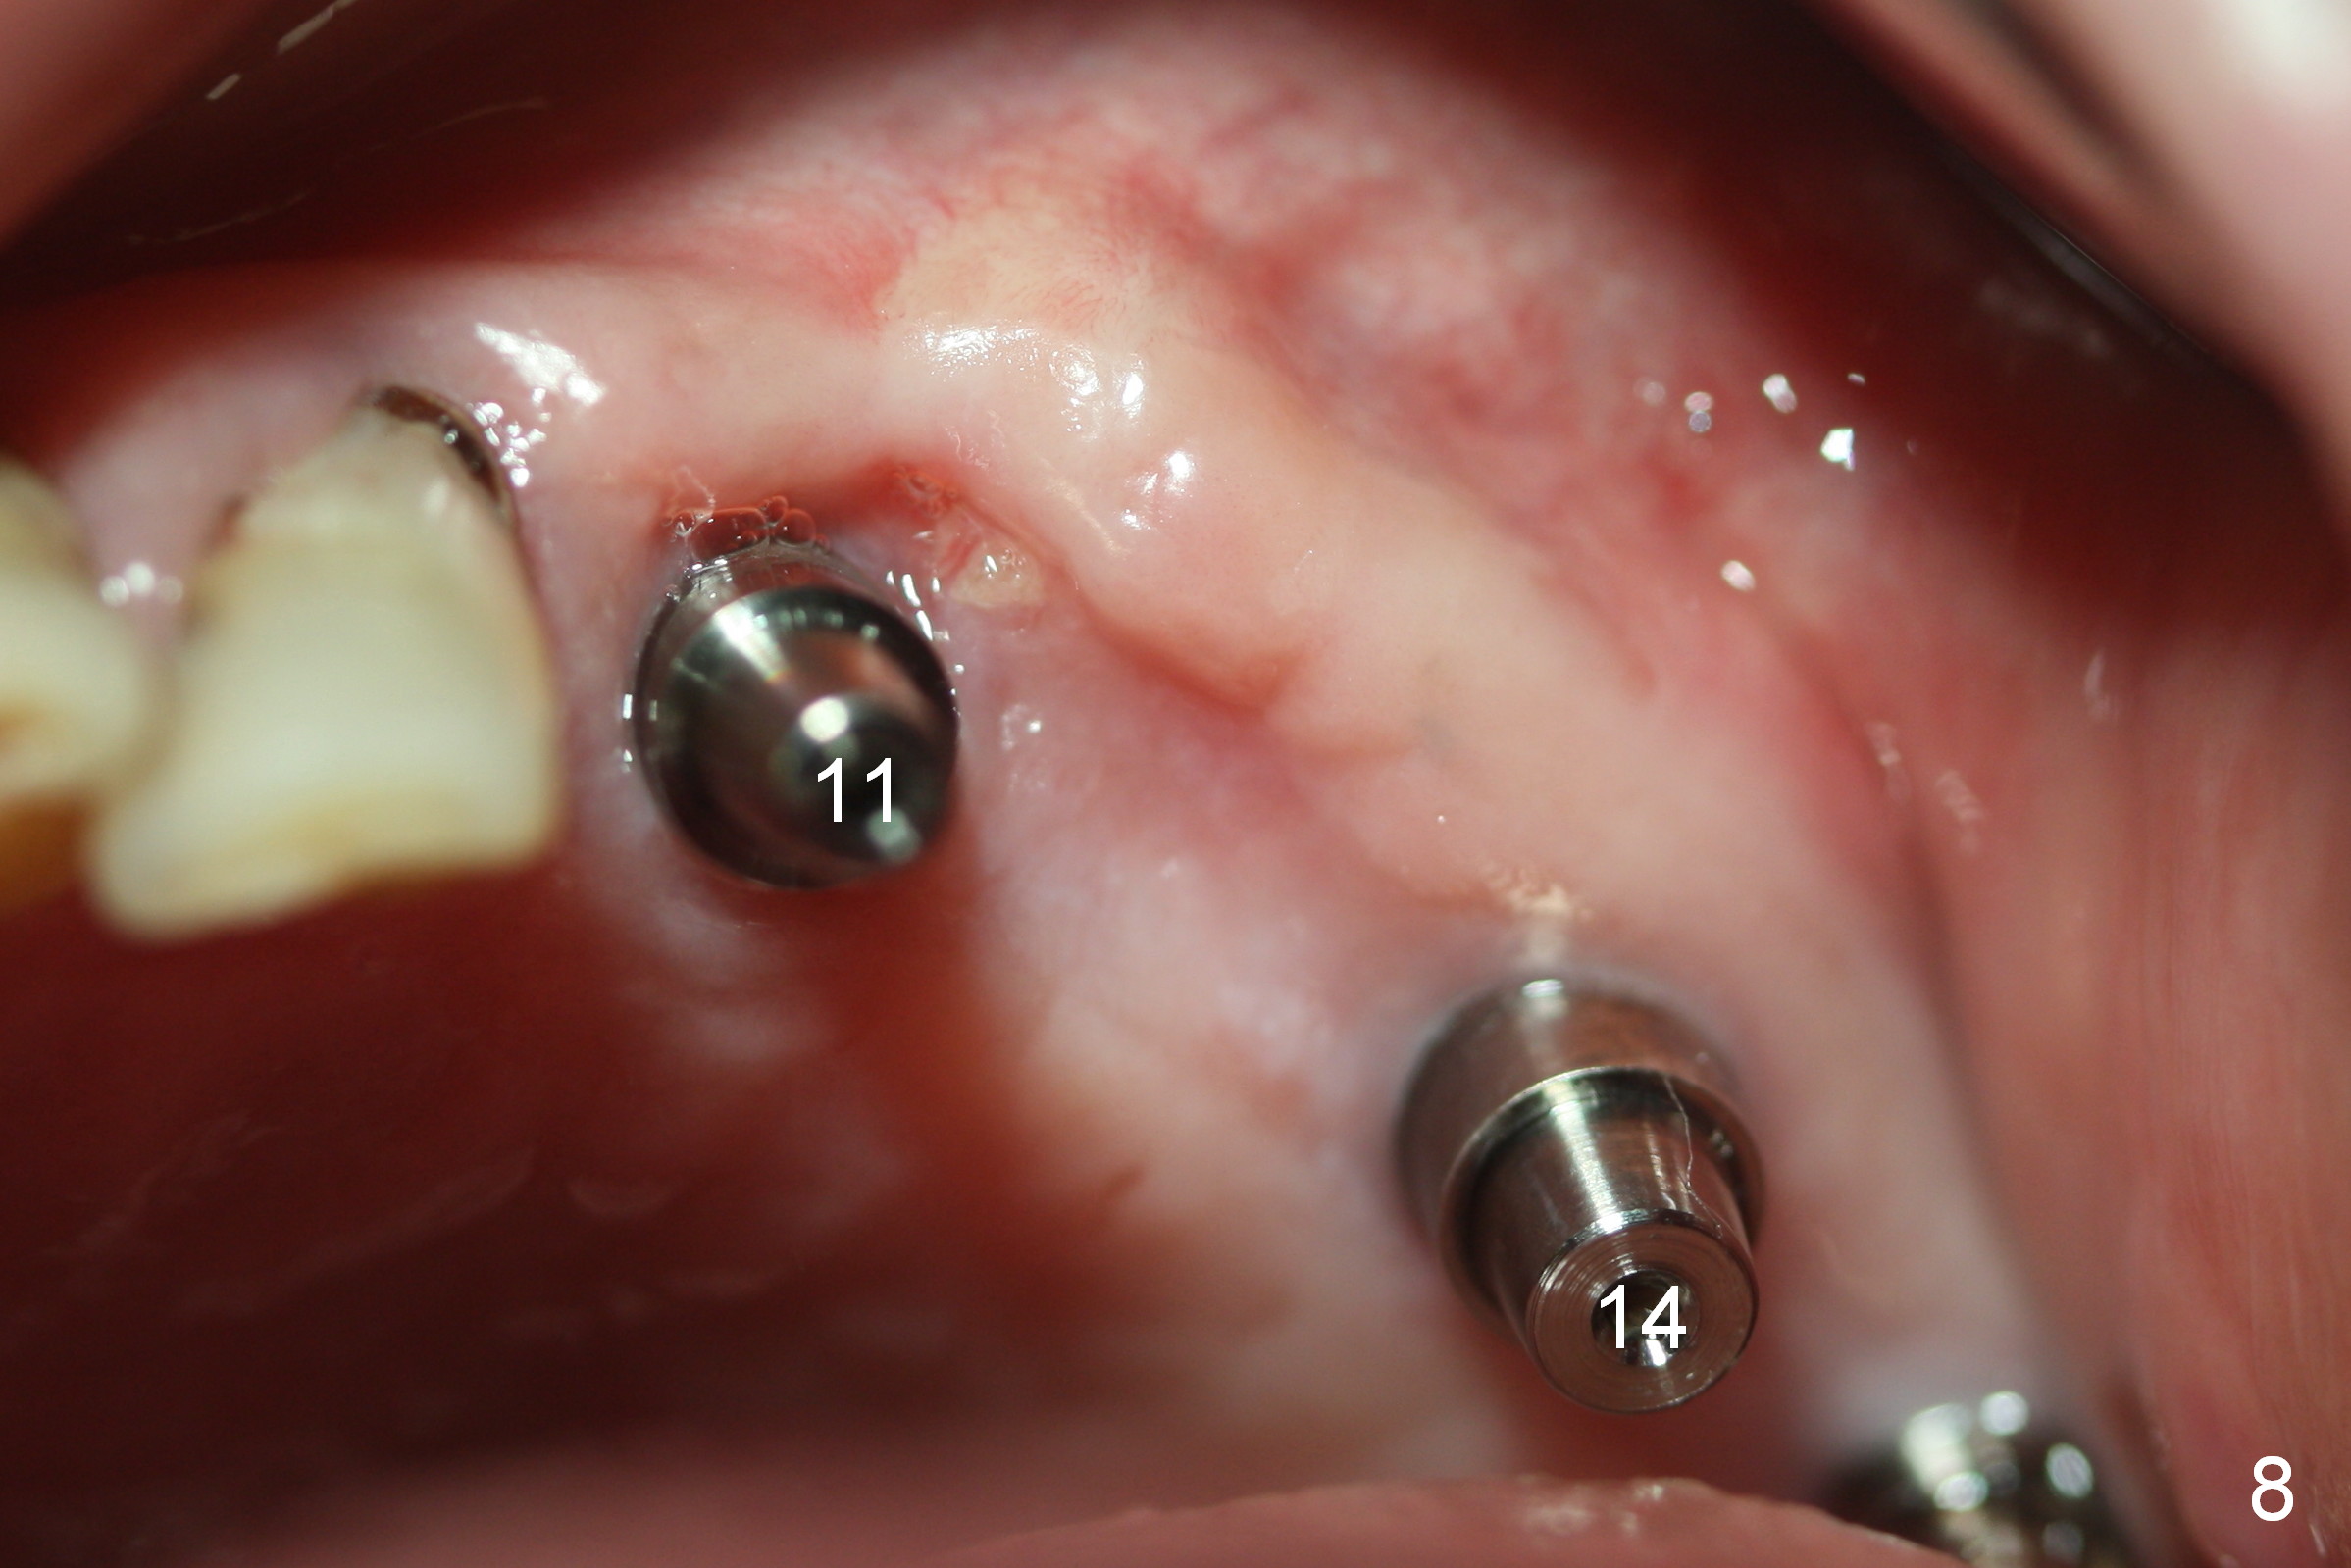

Postop pain is decreasing for 1 month (Fig.8). The ridge is particularly wide. The patient has no interest in getting an implant between those at #11 and 14. After preparation, a splinted provisional is fabricated between #11 and 15.